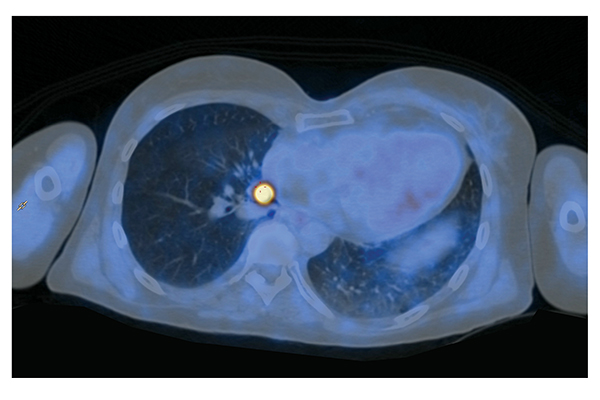

Breast implant-associated anaplastic large cell lymphoma (BIA-ALCL) is a rare CD30 positive T cell lymphoma whose incidence has recently increased. Until 2020, 733 cas...

read article